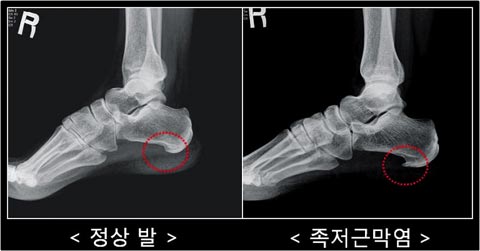

족저근막염 진단

어쨌거나, 어제부로 나는 족저근막염 환자가 되었다 ㅠ

흔히 격한 운동을 해서 발병하는 경우가 많다고 하는데,

나는 해당 사항이 없고, 스트레칭을 너무 안 해서 그럴 거라고 하셨다.